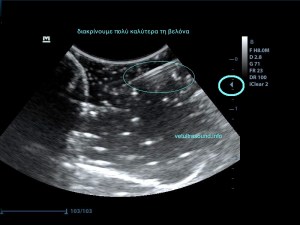

Σημαντικό ρόλο επίσης παίζει η κλίση της βελόνας σε σχέση με τον ηχοβολέα ( κεφαλή ), όσο πιο κάθετη είναι η βελόνα με τον ηχοβολέα τόσο καλύτερη εικόνα της βελόνας έχουμε, όσο αυξάνεται η κλίση τόσο μειώνεται η διακριτική μας ικανότητα.

Λόγω της κλίσης βλέπουμε μόνο την μύτη της βελόνας.

Η βελόνα εμφανίζεται κάθετα προς τον ηχοβολέα.